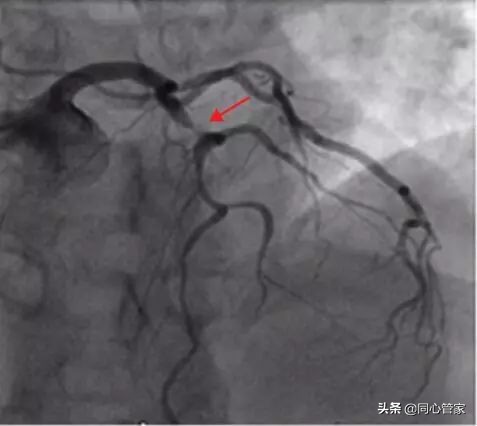

冠脉造影一直被人们称作冠心病诊断的“金标准”,尤其是有心血管疾病、做过支架的患者对造影检查再熟悉不过了。但是今天小编为大家介绍的这种检查,仅需3秒钟就能将血管中的结构、斑块性质、血栓“看”的比造影还清楚——它就是“OCT(中文名称:光学相干断层扫描)”。

冠脉造影:在平时,冠脉造影是诊断冠心病最常用有效的方法,但它只是一个二维平面图像存在一定的局限性,没法让我们了解血管里面发生的情况。